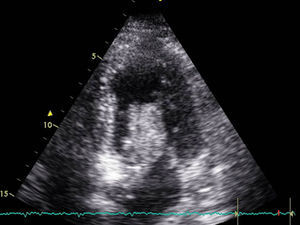

A 68-year-old woman with arterial hypertension and non-insulin dependent diabetes reported to the emergency service due to clinically manifest heart failure for the last two weeks. Upon admission she presented resting dyspnea and palpitations. Rapid atrial fibrillation was detected, requiring pharmacological cardioversion. The echocardiographic study (Fig. 1) revealed a large left atrial mass (1.8×7cm in size) protruding toward the left ventricle and causing secondary mitral valve stenosis and atrial dilatation, with a preserved left ventricular ejection fraction (LVEF). Preoperative coronary angiography showed no lesions.

Transthoracic echocardiography revealed severe left ventricular dysfunction (LVEF<20%), hyperdynamic basal segments and akinesia of the middle and apical segments–these findings being typical of Takotsubo syndrome. There were no significant cardiac enzyme elevations over the following days (taking surgery into account), with a maximum ultra-sensitive troponin I concentration of 4000pg/ml (normal 2–15.6pg/ml). In contrast, the electrocardiographic tracing showed significant changes with respect to the previous recordings, with a long QTc (680ms) and the appearance of inverted T-waves on precordial leads during several days (Fig. 2). The electrolyte profile and rest of the laboratory test parameters were normal.